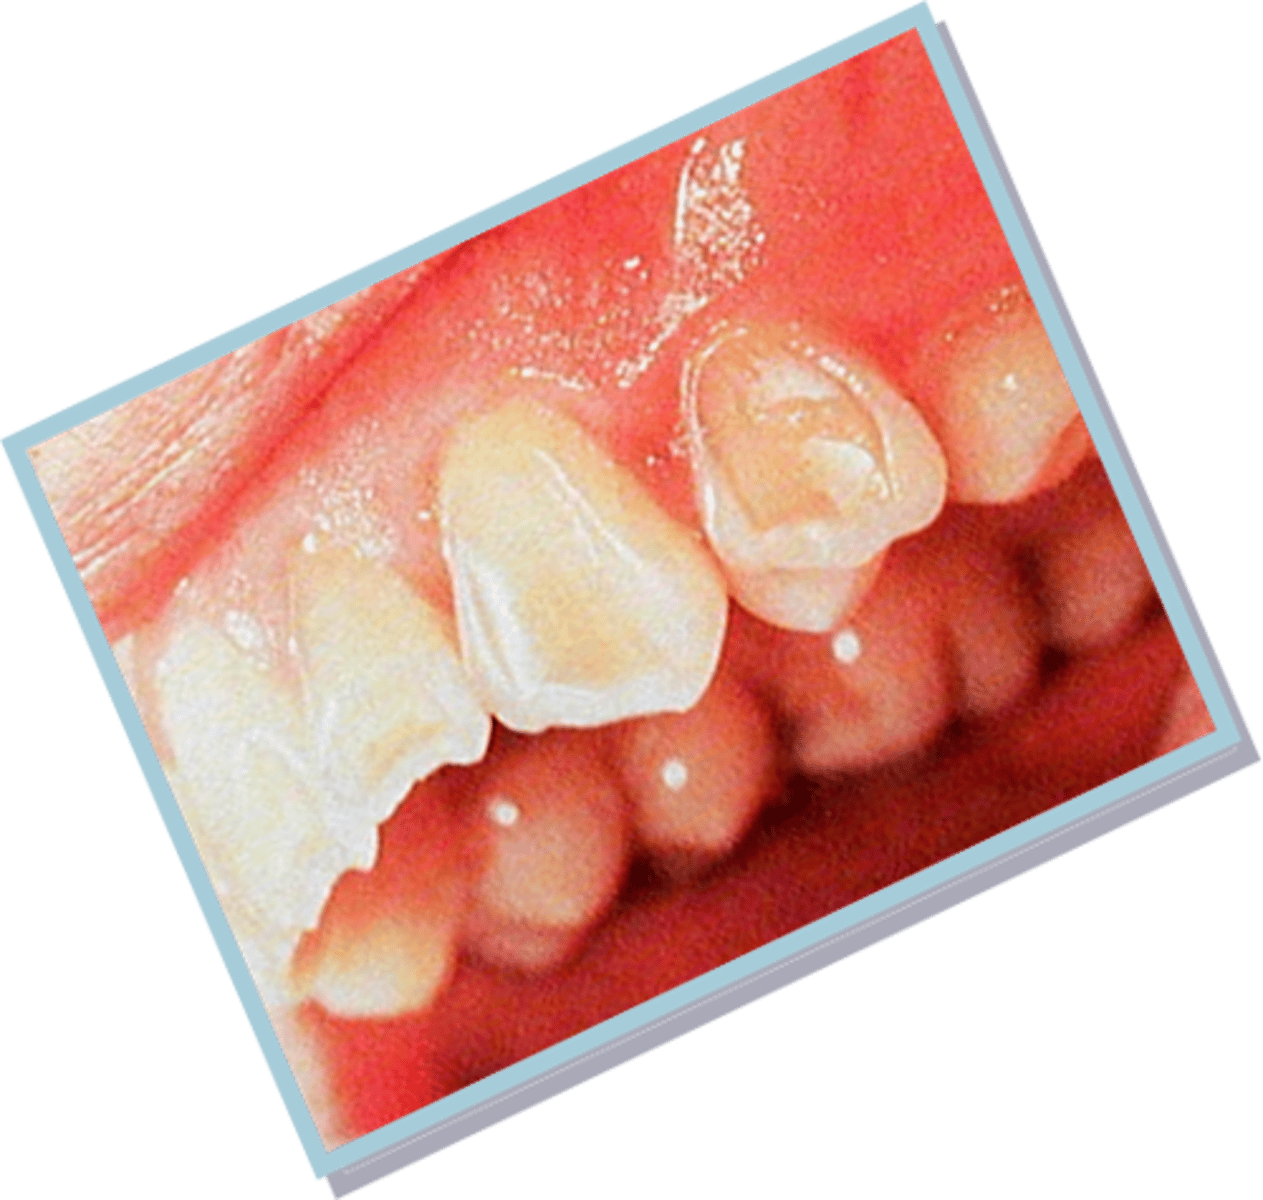

Diagnose amelogenesis imperfecta radiographically

(on 2024 exam)

- smaller than normal teeth

- yellow or brown discoloration

- teeth prone to damage, breakage

- sensitive teeth

- open bite malocclusion

- minimal to no enamel visible radiographically

Diagnose dentinogenesis imperfecta radiographically

- bulbous crowns

- cervical constriction

- thin roots

- early obliteration of root canals and pulp chambers

Once thought to be associated with BLUE SCLERA and multiple bone fractures